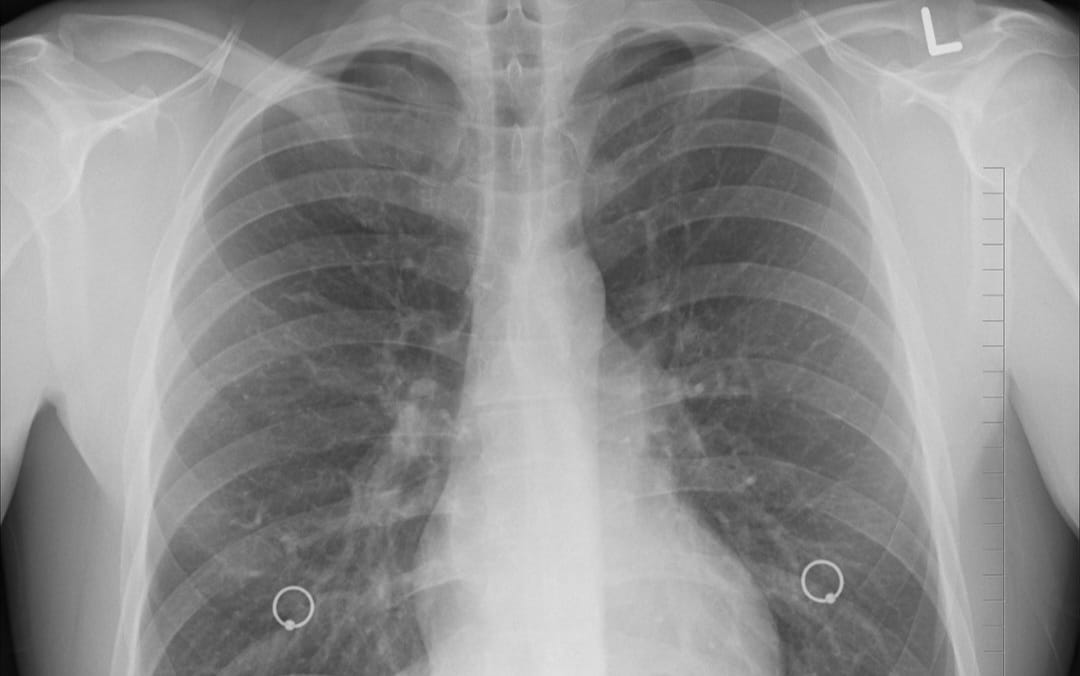

“Yuk warga Depok, cek kondisi paru-paru anda secara gratis di 20 Puskesmas di Kota Depok yang sedang melaksanakan skrining kesehatan paru dengan pemeriksaan radiografi toraks (rontgen dada),” tulis Dinkes Kota Depok lewat unggahan akun Instagram resmi @dinkeskotadepok, dikutip Kamis (9/10/2025).

Pemeriksaan radiografi toraks sangat penting, terutama bagi mereka yang sering terpapar polusi udara, perokok, atau memiliki gejala pernapasan seperti batuk berkepanjangan. Melalui skrining ini, warga dapat memastikan paru-paru tetap sehat dan mendeteksi masalah kesehatan yang mungkin tidak terlihat tanpa pemeriksaan.